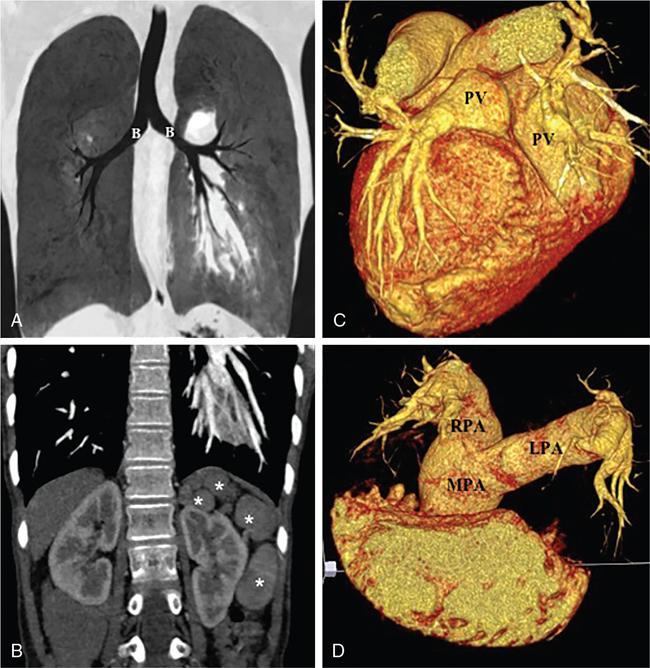

Kalpana Bansal, Poonam Narang The paediatric splenic abnormalities include both congenital and acquired pathological conditions. The congenital anomalies include variations in splenic number, location or fusion abnormalities and are more common than the acquired pathological conditions like splenomegaly, focal lesions, tumours and trauma. The splenic pathology can be evaluated with a wide variety of available imaging modalities including an ultrasound that is usually the first modality of choice in paediatric patients, computed tomography, magnetic resonance imaging and technetium-99m scintigraphy. The pattern-oriented approach to the radiological evaluation of splenic abnormalities may help to reach an accurate diagnosis and plan patient management. The congenital anomalies are common splenic abnormalities in paediatric patients. They usually result from absent or incomplete fusion of splenic lobules into one single organ before birth or abnormal location of the spleen. The congenital malformations include: The accessory spleen is commonly referred to as the splenunculus or supernumerary spleen. It results from the failure of the fusion of the primordial splenic buds in the dorsal mesogastrium during foetal life. The incidence is seen in 10%–30% of the population. The most common location of an accessory spleen is near the splenic hilum seen in about 75% of the cases and the pancreatic tail in 25% cases. It may be located anywhere along the course of the splenic vessels or in the abdomen and pelvis. The size of an accessory spleen ranges from few millimetres to centimetres and the number may vary from 1 to 6 (Fig. 9.21.1). The accessory spleens are usually asymptomatic and incidentally detected on imaging. But an accessory spleen present in an unexpected location can be misinterpreted as an abnormal soft tissue mass or lymph node. The characteristic imaging findings of the accessory spleen include similar imaging appearance to normal spleen on CT and MRI. The demonstration of feeding artery from the splenic artery can also be helpful in the differential diagnosis. Iron-containing MR contrast agents and Tc-99 sulphur colloid scintigraphy may be useful to confirm the diagnosis. The clinical significance of accessory spleen is seen in patients who had splenectomy for hypersplenism. In such patients, the accessory spleen may hypertrophy and result in recurrent disease; however, in patients of splenic trauma who had a splenectomy, it may help preserve the immune functions of the spleen. Splenopancreatic fusion is a rare anomaly that results due to abnormal fusion of splenic or pancreatic tissue as both organs arise from the dorsal mesogastrium close to each other. The ectopic splenic tissue may be located in the pancreatic tail (Fig. 9.21.2) and ectopic pancreas in the spleen or accessory spleen. It is also an incidental finding and asymptomatic. The clinical importance is to avoid complications during splenectomy or distal pancreatectomy. Splenogonadal fusion is an extremely rare anomaly that results due to the persistence of splenic tissue between the spleen and left testicle or epididymis. It may simulate masses and warrant unnecessary surgeries. The demonstration of splenic tissue connecting the spleen with the left gonad using any of the imaging modality helps in definitive diagnosis. Wandering or ectopic spleen is an extremely rare entity that results due to laxity or maldevelopment of the supporting splenic ligaments, and spleen can be found in any part of the abdomen. The incidence in several large studies of splenectomy is less than 0.5% and is mainly seen in children. The wandering spleen may be detected incidentally or present with different degrees of abdominal pain related to intermittent or acute torsion of the vascular pedicle. Ultrasound and CT remain the mainstay of diagnosis. Imaging findings include the absence of spleen in its normal position and a mass located anywhere in the abdomen or pelvis showing imaging and enhancement characteristics of normal splenic tissue. Besides, in the case of torsion, a typical ‘whirl’ pattern of the twisted pedicle and altered enhancement may also be demonstrated. Doppler shows absent flow within the spleen and low diastolic velocity with raised resistive index in the proximal splenic artery. The unenhanced CT shows hypoattenuation of the spleen, hyperdense intraluminal thrombus in the splenic artery and high density of the splenic capsule relative to parenchyma (‘rim’ sign). The contrast-enhanced CT shows absent or heterogeneous enhancement. The treatment modality of choice is splenopexy; however, splenectomy may be indicated in cases of infarction. Polysplenia and asplenia are typically seen in association with situs ambiguous or heterotaxia. Situs ambiguous with asplenia also known as Ivemark syndrome refers to right isomerism or bilateral right-sidedness and is characterized by an ambiguous location of abdominal organs with congenital absence of the spleen. It is more prevalent in males and associated with congenital heart disease in almost all cases (Fig. 9.21.3). Most patients die within the first year of life due to associated severe congenital heart disease and immunodeficiency due to absent spleen. Situs ambiguous with polysplenia is referred to as left isomerism or bilateral left sidedness. It is more common in females. The spleen may be located on the left or right side of the upper abdomen, the number may vary from 2 to 6 and diameter ranges from 1 to 6 cm (Fig. 9.21.4). The coexisting anomalies include a right-sided stomach, a midline or left-sided liver, bowel malrotation, short pancreas, absent gallbladder and associated inferior vena cava anomalies. Splenosis is an acquired anomaly that occurs following splenic trauma or splenectomy. It results due to auto-transplantation of splenic tissue usually in the peritoneal cavity but also may occur in extraperitoneal locations like the thoracic cavity. Splenosis is usually asymptomatic and incidentally detected on imaging. Splenosis is an acquired condition so it has distorted architecture and is supplied by surrounding vessels so, it can be mistaken for neoplastic lesions and lead to unnecessary surgery. A patient who had splenectomy for hypersplenism, splenosis may result in recurrent disease. However, a functioning splenic tissue may be required to preserve normal immunological function and remove old blood cells. Splenomegaly is a nonspecific finding seen as a manifestation of various disease processes listed in Box 9.21.1. CAUSES OF SPLENOMEGALY Ultrasound is usually the first and useful modality to evaluate enlarged spleen. It accurately measures the splenic span and also assesses the splenic echotexture, homogeneous or heterogeneous. Doppler USG is very good for the assessment of portal hypertension as a cause of splenomegaly by demonstrating flow in the splenoportal axis and collaterals. Both USG and CT also assesses the ancillary findings like lymphadenopathy in case of lymphoma or tuberculosis. Portal hypertension is one of the most common noninfectious causes of splenomegaly in children. Patients usually present with significant gastrointestinal bleed or massive splenomegaly. The causes of portal hypertension may be prehepatic, intrahepatic or posthepatic. The portal vein thrombosis is mostly idiopathic in children and results in collateral vessel development at porta known as cavernous transformation of the portal vein or portal cavernoma and portosystemic collaterals with massive splenomegaly (Fig. 9.21.5).